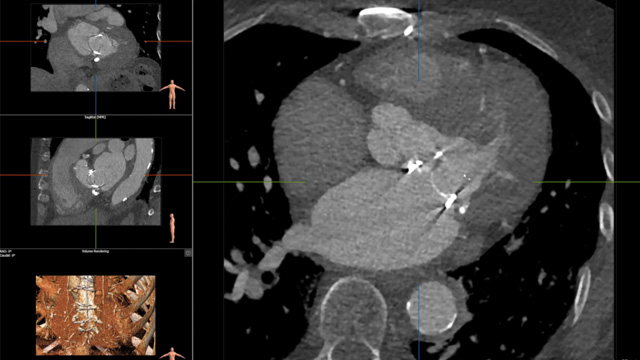

M-TEER for challenging anatomy

09 Feb 2025 – From PCR Tokyo Valves 2025

Delve into the world of M-TEER for challenging anatomies. Understand the types of complex anatomies, the associated risks of complications, and learn how to select the appropriate TEER strategy for patients with small left atria, large gaps, and giant left atria. Gain valuable insights to optimize...